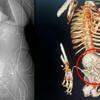

O caso clínico da menina é descrito pela medicina como fetus in fetu (FIF) ou gêmeo parasita. No caso da criança, o feto tinha cerca de 18 centímetros e já havia desenvolvido braços, cabelos e olhos. A anormalidade foi registrada no American Journal of Case Reportno, no dia 21 de junho.

A condição da garota é considerada rara, tendo apenas 20 casos registrados na história. A anomalia consiste no desenvolvimento de um resquício de embrião ou feto dentro do corpo do irmão gêmeo, com a junção dos corpos de forma semelhante à de gêmeos siameses, mas com a total assimilação do corpo de um pelo outro e isso geralmente ocorre dentro da região do abdômen.

Ao realizarem uma ressonância, os médicos pensaram que a cápsula que as defesas do corpo da menina tinha feito ao redor do feto se tratava de um tumor de grandes proporções. Após exames mais detalhados, os resultados apontaram a presença de ossos, indicando que se tratava de um feto mal-formado.

Como o feto estava comprometendo o cérebro da criança, foi necessário realizar uma cirurgia, pois, essa é a única forma para tratar casos de FIF. No meio do procedimento, os médicos descobriram que além do gêmeo parasita, vários tumores se desenvolveram ao redor de onde estava o feto.